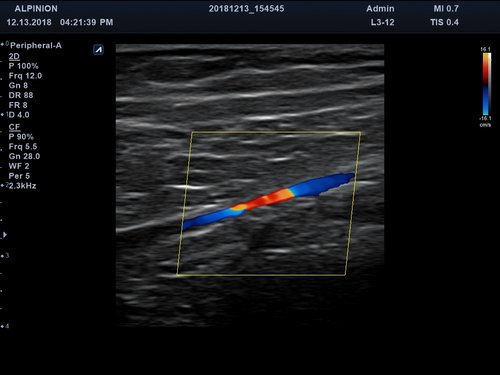

Anwendungsbereiche Abdomen MSK, Nerven, Karotis, periphere Gefäße, Schilddrüse, Mamma

Bildgebungs-Modi B-Modus, CF, M, PW, PD B-Modus, CF, M, PW, PD

• Farbdoppler: farbige Darstellung der Richtung des Blutflusses